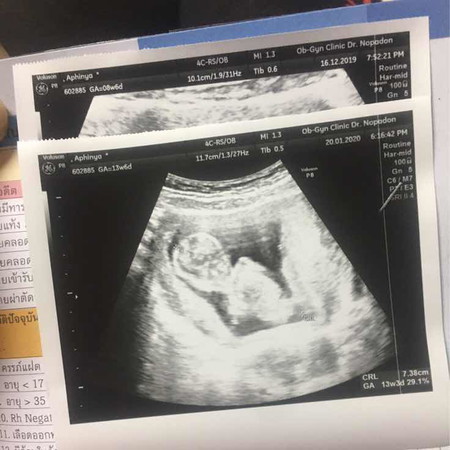

ของเราพึ่งซาวมาวันนี้ 13w3d น้องยาว7.38 แร้วว ดิ้นเก่งมากๆค่ะ ตื่นเต้นมาก ยิ้มไม่หุบเลย?

ตอน3เดือนค่ะ ตอนนี้30วีคแล้ว

น้องร่าเริงค่ะ ดิ้นเก่ง